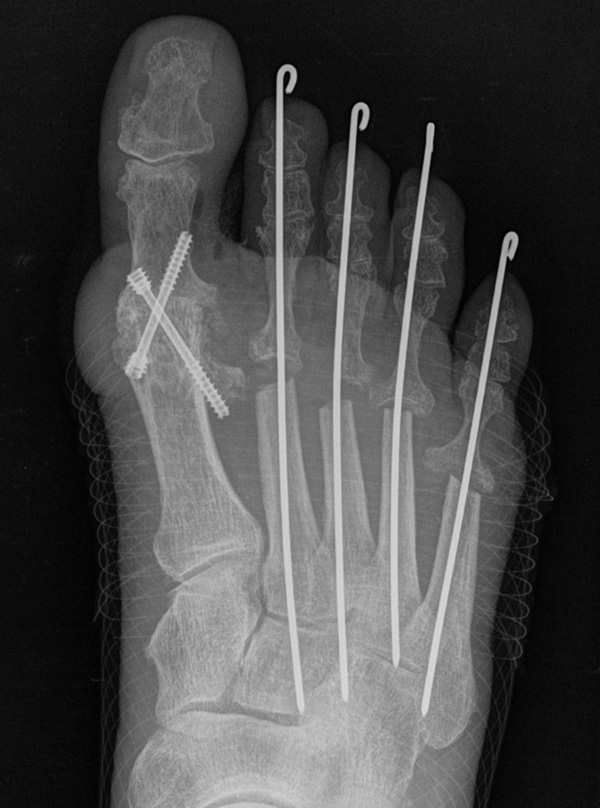

Deutlich bessere Ergebnisse wurden erreicht durch eine Kombination der OP nach Tillmann mit einer Arthrodese des Großzehengrundgelenks oder auch einer Lapidus-Arthrodese 611. Dies wurde bereits 1956 durch Vainio empfohlen, hat sich aber erst in diesem Jahrtausend flächendeckend durchgesetzt 121314.

Abschließend erfolgt die temporäre K-Daht Fixation sämtlicher Kleinzehen in achsgerechter Stellung. Die Strecksehnen werden in Verlängerung vernäht.

Die Arthrodese des Großzehengrundgelenks in Kombination mit einer Resektionsarthroplastik der Metatarsaleköpfchen der Kleinzehen führt zu guten klinischen Langzeitergebnissen bei Patienten mit rheumatoider Arthritis und destruiertem Metatarsaleköpfchen 34. Auch aktuelle Metaanalysen zeigen, dass dieses Verfahren den Standard bei dieser Pathologie darstellt und dass sich insbesondere auch gelenkerhaltende Therapieverfahren an diesen Ergebnissen messen müssen 35. Triolo et al. 11 berichteten über die Ergebnisse von 89 Füßen (62 Patienten) mit einem Follow up von mindestens 4 Jahren. Der AOFAS Score verbesserte sich nach Arthrodese am Großzehengrundgelenk und OP nach Tillmann Metatarsale II-V von präoperativ 33,4 ±16 auf 82,9 ± 11,9 Punkte. Schlechte Ergebnisse wurden beobachtet bei Patienten mit Revisionseingriffen aufgrund von Pseudarthrosen, verzögerter Knochenheilung, ungenügender Knochenresektion der Metatarsalia und störendem Osteosynthesematerial. Hulse et al. 36 verglichen die Ergebnisse nach Tillmann OP mit und ohne gleichzeitiger Resektion des Metatarsale I Kopfes. 44% der Patienten bei welchen das Großzehengrundgelenk erhalten wurde benötigten im 5-Jahres Follow-up einen weiteren Eingriff an diesem Gelenk. Die Autoren empfahlen daher, das Großzehengrundgelenk in jedem Fall in das Therapiekonzept einzubeziehen. Eine Langzeit Kohortenstudie an 203 Patienten (370 Füße) mit einem Follow-up von 11,4 Jahren wurde von Jüsten et al. veröffentlicht 10. 90,2% der Patienten berichteten über eine signifikante Besserung der Beschwerden, 87,5% über eine Besserung der Gehstrecke.